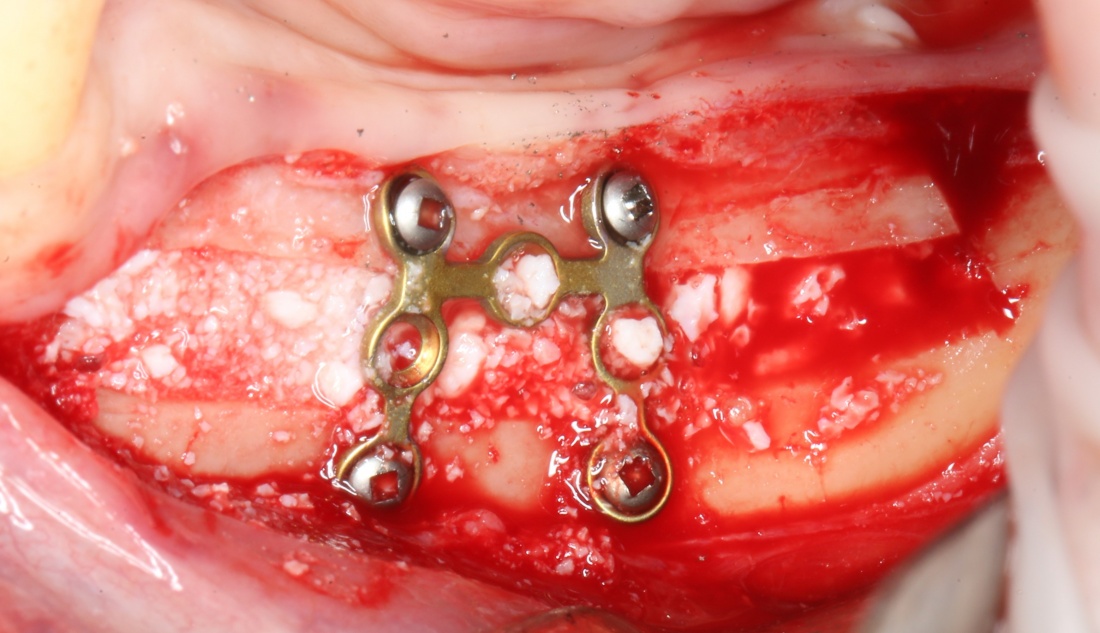

Изоляция области аутографта и имплантатов барьерной мембраной.

Перекрывать костный блок барьерной мембраной или оставить так? По этому вопросу есть много мнений. Между тем, в публикации по методике есть ясное показание, когда это требуется.

Конкретно в этом клиническом случае между костным аутотрансплантатом, ложем и имплантатами есть пустое пространство. Если его не изолировать от мягких тканей, они прорастут и осложнят интеграцию аутографта. Поэтому я решил перекрыть костный блок барьерной мембраной, пусть это делает хирургическую операцию немного дороже.

— ты знаешь, что барьерная мембрана может выполнять две функции, каркасную и изолирующую. Первая функция требует обязательной фиксации и натяжения, вторая — нет. В нашем случае «каркасом» регенерата является костный блок, а барьерная мембрана нужна только для изоляции. Поэтому она не требует натяжения и фиксации пинами.

После я внимательно проверил, что костный блок и имплантаты полностью перекрыты. Теперь рану можно ушивать.